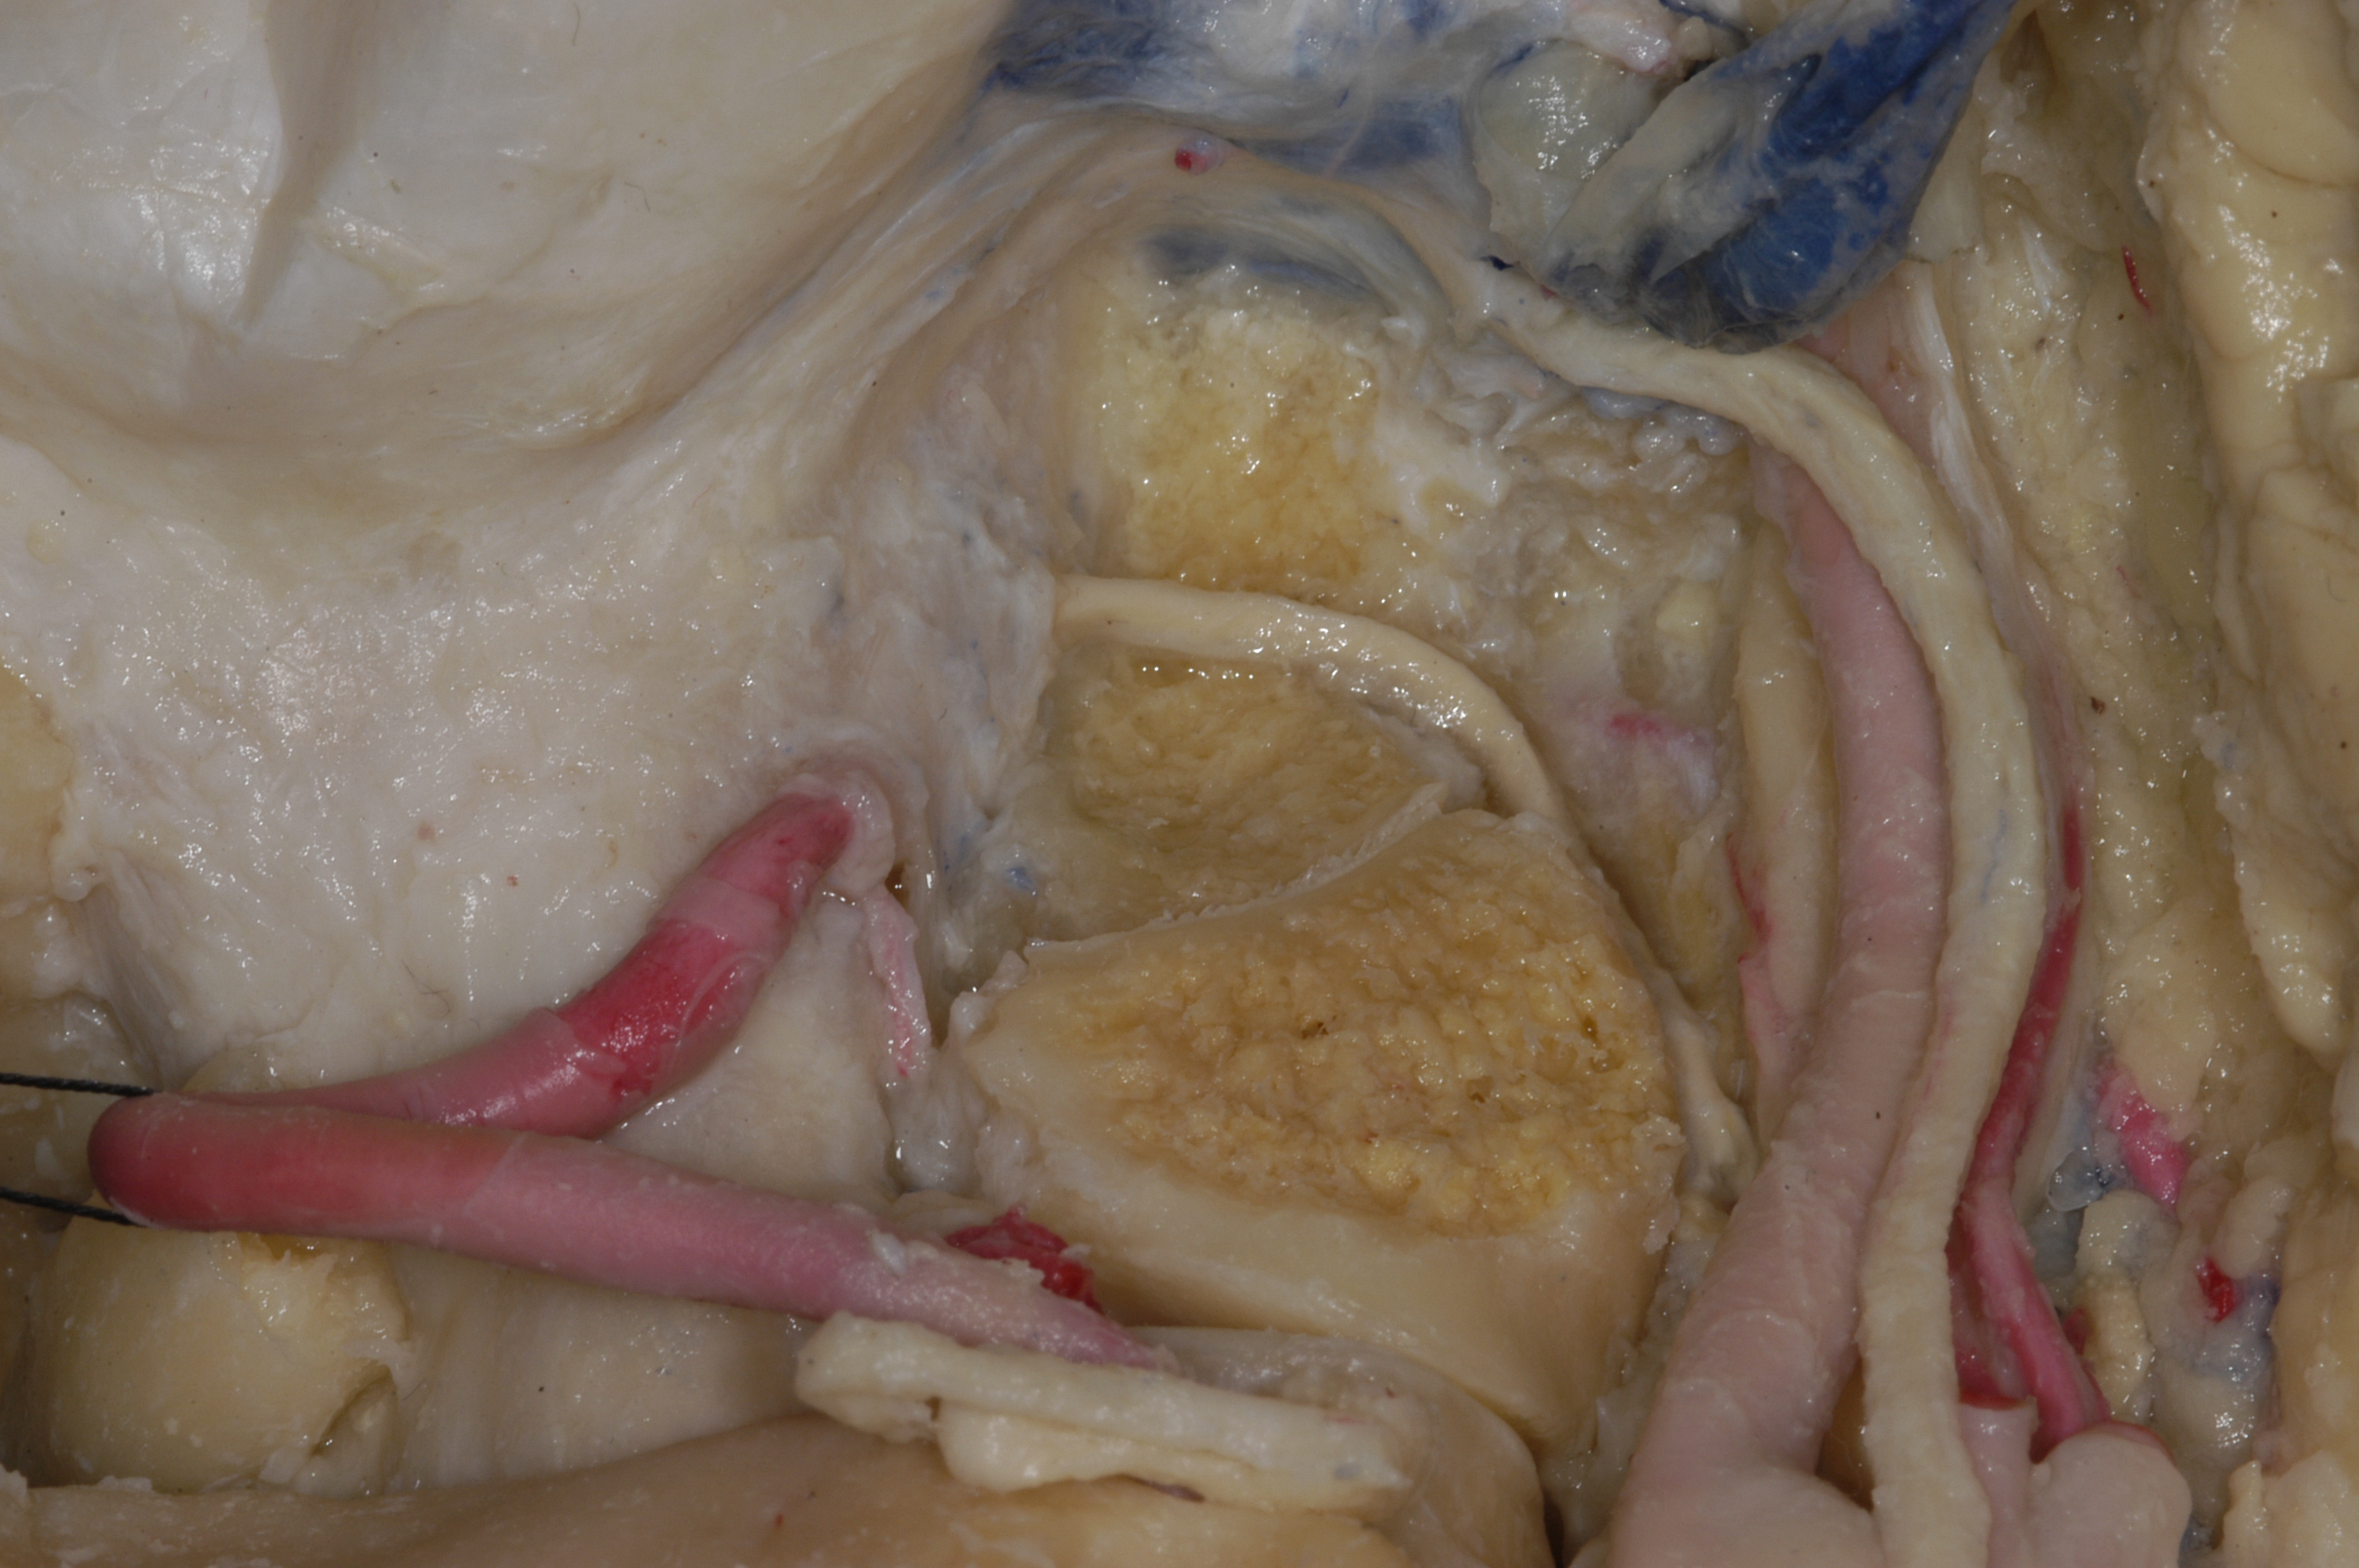

这个是手术过程,实践中感觉舌下神经管鞘瘤越小,越难暴露。